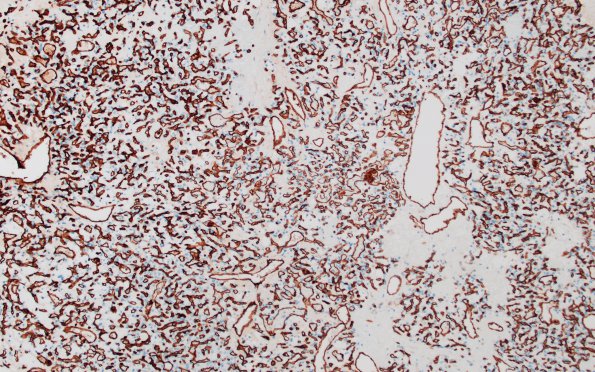

2C Hemangioblastoma (Case 2) CD31 2

CD31 highlights an extensive vascular proliferation within the tumor. (CD31 IHC)